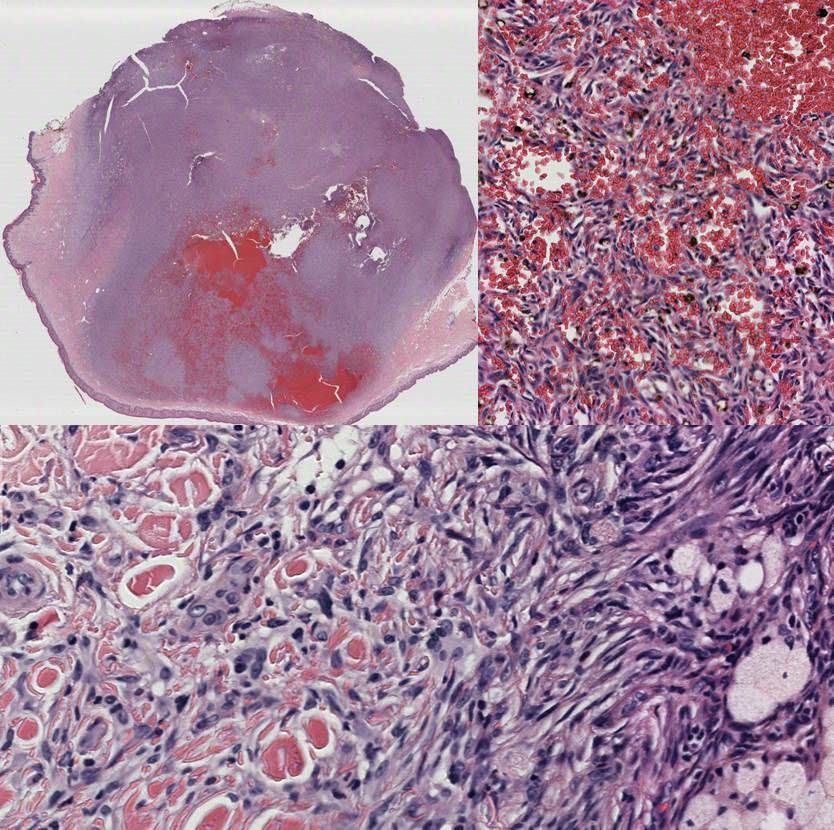

30 yo female with enlarging calf nodule.

Dermatofibroma with aneurysmal change